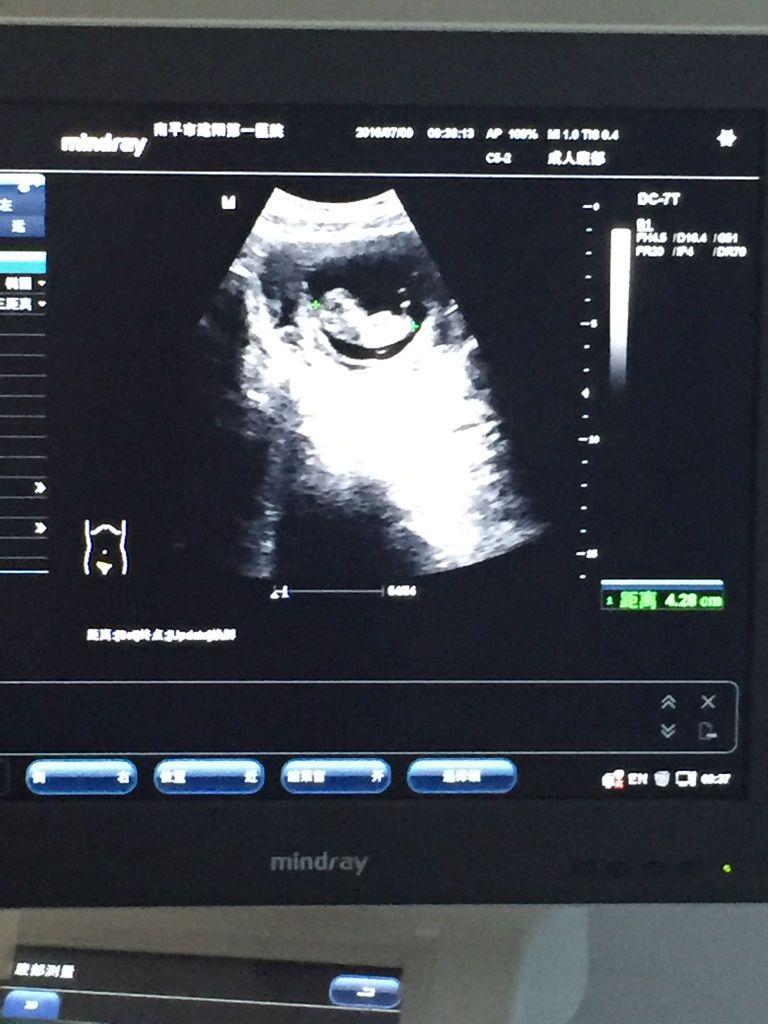

怀孕70多天,B超单怎么分辨生男孩可能性大还是生女孩可能性大呢,男女我都喜欢,就是很好奇 点击展开 匿名用户 2016-07-09 10:46 为您推荐: 其他回答 三个月看的不是很准,建议二十四周之后再看 匿名用户 2016-07-09 10:54 相关问题 b超怎么才能看出男孩还是女孩可能性大? 请专业医生给看看男孩女孩!呵呵!因好奇!今天做了B超大排畸 我的孕囊是3 4cm*3 8cm*1 1cm,请问是男孩是女孩?男女都一样,只是好奇,宝宝太神秘了~-~